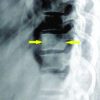

A 32-year-old female came with complaints of mid backache, left wrist pain, left arm pain, and deformity. Patient had a history of fall from 3rd floor. On examination, tenderness was present over mid back, left wrist and arm. Left upper limb radial pulse was absent with normal pinprick and capillary refill. X-ray of the LS spine, wrist and arm revealed the L2 compression fracture with left distal radius dorsal Barton’s fracture and left humerus shaft oblique fracture with one small bony fragment lying anterior to the fracture (Fig. 5). CT angiography of the left upper limb revealed left brachial artery short segment luminal narrowing, and partial contrast opacification around the fracture site (Fig. 6).